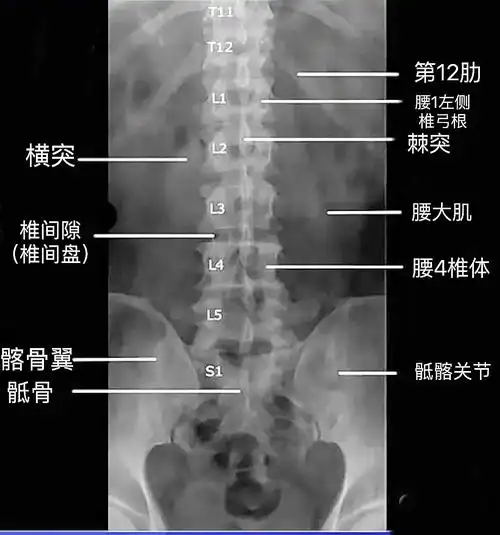

人体腰椎x线影像图片下载

教会您阅读看懂腰椎x线片(一),干货满满,献给需要的朋友!